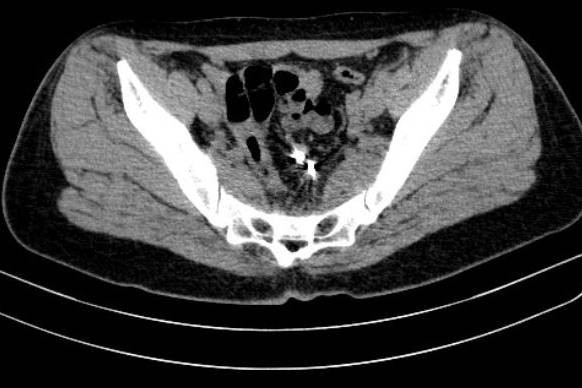

Sau khi có kết quả xét nghiệm, chiếu chụp, các bác sĩ quyết định phẫu thuật để lấy vòng tránh thai lạc chỗ và xử lý chỗ thủng đại tràng cho người phụ nữ này. Bệnh nhân được xuất viện sau 6 ngày.

Tuy nhiên, dụng cụ tử cung có thể di chuyển xuyên thủng tử cung với tỷ lệ từ 1,3-1,6/1.000 lần đặt. Sau khi xuyên qua tử cung, dụng cụ này có thể rơi vào ổ bụng tự do hoặc nằm trong khung chậu, hoặc có thể xuyên thủng tiếp vào các cấu trúc lân cận như bàng quang, đại tràng, ruột non và hình thành các đường rò tử cung - bàng quang hoặc tử cung - ruột.